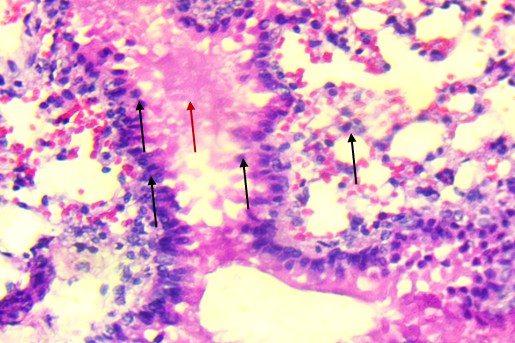

In the mid-dose group (0.7 mg/kg), histopathological changes became more apparent. The alveolar septa were mildly thickened, and there was evidence of focal inflammatory infiltration, particularly in the peribronchiolar regions. These findings suggest early-stage toxic alveolitis, possibly mediated by oxidative or inflammatory mechanisms triggered by the plant’s alkaloids. The high-dose group (4 mg/kg) revealed the most prominent pulmonary lesions.

Bronchiolar epithelium appeared partially detached, and several lung sections displayed eosinophilic proteinaceous material within the airway lumens. Alveolar spaces were noticeably reduced, and focal hemorrhages were present, indicating increased capillary permeability or endothelial injury (Figure 3).

|

A. Control: Normal alveoli and septa. |

B. T1: Comparable to control with minimal epithelial irregularities. |

C. T2: Septal thickening and peribronchiolar infiltration. |

D. T3 epithelial detachment. |

E. T3 intra-alveolar hemorrhage. |

F. Representative treated: Multifocal hemorrhage and inflammation. |

Figure 3. Lungs of Swiss albino mice: (A) Control with intact alveoli, (B) T1 minimal changes, (C) T2 septal thickening, (D) T3 epithelial detachment, (E) T3 intra-alveolar hemorrhage, (F) Representative treated lung with multifocal hemorrhage.

Despite the severity of these findings, there was no widespread consolidation or fibrotic remodeling, implying that the damage remained in the acute, potentially reversible phase. Animals from the recovery group that received the high dose followed by a treatment-free period showed partial resolution of pulmonary lesions. While some inflammatory features had regressed, mild septal thickening and epithelial irregularities persisted, indicating incomplete histological recovery within the observation window.

In contrast to the heart, the lungs exhibited apparent dose-related histological alterations (Figure 3). In control animals (Figure 3A), pulmonary tissue appeared intact with open alveolar spaces, thin interalveolar septa, and unremarkable bronchiolar epithelium. This structure was mainly preserved in the low-dose group (Figure 3B), with only minor irregularities. However, lungs from the mid-dose group (Figure 3C) began to show mild septal thickening and peribronchiolar inflammatory infiltration, indicating the onset of localized alveolar injury.

At the highest dose (Figures 3D and 3E), the lung tissue revealed more severe pathology, including bronchiolar epithelial detachment, eosinophilic deposits, reduced alveolar spaces, and focal hemorrhage. These findings suggest a toxic alveolitis-like response, potentially driven by a combination of muscarinic receptor blockade, which can impair airway regulation and mucosal secretions, and oxidative stress, which may provoke capillary leakage and inflammatory activation. Similar histological patterns have been reported in experimental and forensic studies of acute Datura intoxication, often correlating with respiratory distress or pulmonary edema observed at autopsy (Boumba et al., 2004; Le Garff et al., 2016; Shifa et al., 2024).

Of particular interest, lungs from recovery animals (Figure 3F) showed partial resolution of lesions. Although inflammation was reduced and some epithelial reorganization had occurred, residual septal thickening persisted, indicating that while some of the extract’s pulmonary effects are reversible, complete histological recovery may require a more extended withdrawal period or additional therapeutic support. This partial reversibility aligns with clinical cases in which respiratory symptoms improve following cessation of exposure and supportive care.